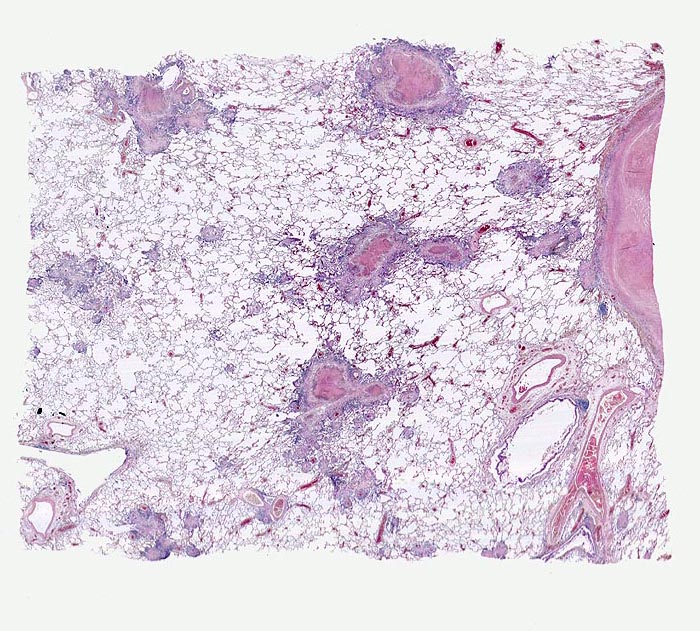

azinös-nodöse Lungentuberkulose

Die Granulome sind jeweils in unmittelbarer Umgebung einer Arterie lokalisiert. Die tuberkulösen Herde gehen aus von vollständig oder partiell entzündlich zerstörten Bronchiolen (bronchogene Streuung). Die Granulome bestehen aus einer zentralen käsigen Nekrose umgeben von einem helleren Epitheloidzellwall und ganz aussen einem blauen Saum von Lymphozyten.

Die chronische produktive azinös-nodöse Tuberkulose entwickelt sich, wenn bei bronchogener Keimstreuung die Abwehrlage gut ist. Das käsige Exsudat imponiert makroskopisch als kleeblattartige oder knotige weisse Herde, die dem bronchoalveolären System entsprechen.